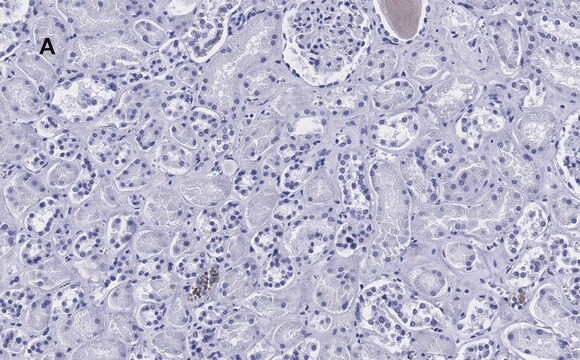

Immunohistochemistry (Paraffin) Analysis: A 1:100 dilution from a representative lot detected HSP60 in human kidney and mouse kidney tissue sections.